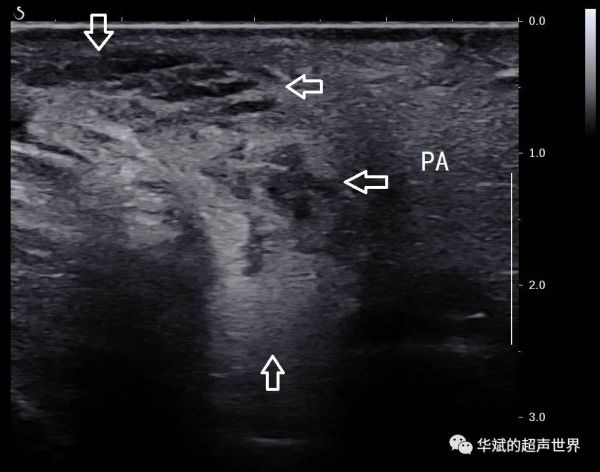

我们对该区域行超声检查,发现局部皮下组织和腮腺的后上部分内为大量的蜂窝状回声,彩色多普勒和能量多普勒均显示其内为及其丰富的血流信号(酷似血管瘤),可探及低速动脉血流。(下三图,PA:腮腺)

我们推测,腮腺内及腮腺周围的这些病变也可能是艾瑞卡引起的血管增生症的表现,尽管之前的研究中仅仅提到这种反应性毛细血管增生症主要发生在皮肤和粘膜。这一病例提示我们在艾瑞卡使用者中,其他深层组织内也可能会出现反应性毛细血管增生症。